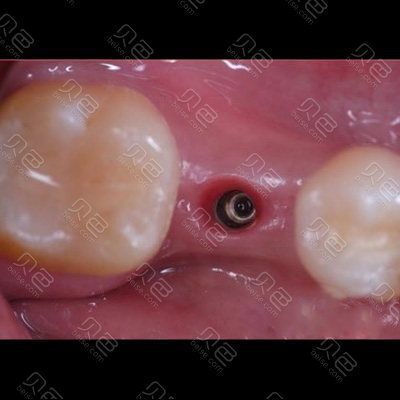

(图片来源网络,侵删)- 创伤最小化: 微创种牙的核心目标是显著减少手术创伤,这体现在切口更小(甚至无切口)、翻瓣范围更小、骨组织去除更少、对软硬组织损伤更轻。

- 专用微创器械: 采用更细的种植体、更精细的手术器械(如微创环切器、细径钻头等),进一步减少组织损伤。